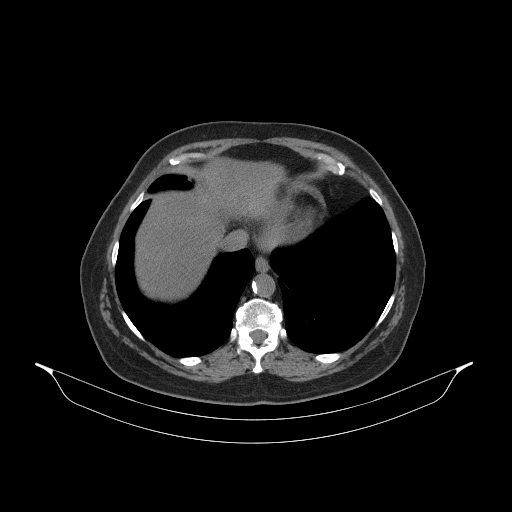

Reconstructed NATIVE CT scan (cycle consistency)

Full window (WL 1023.5, WW 4095 β†’ Low βˆ’1024, High +3071)

Actual HU range: [-1024.0, 1184.6]

Lung window (WL -600, WW 1500 β†’ Low βˆ’1350, High +150)

Actual HU range: [-1108.2, 150.0]

Mediastinum window (WL 40, WW 400 β†’ Low βˆ’160, High +240)

Actual HU range: [-160.0, 240.0]